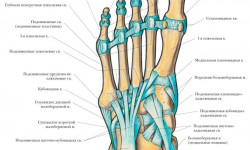

Онихолизис бывает: частичным, когда признаки отслоения на ногтях ног или рук появляются только с одной стороны, например, вдоль бокового кожного валика (в этом случае говорят о боковом онихолизисе); полным, когда отслойка ногтя происходит по всей его площади.

Онихолизис — это отслоение ногтевой пластины от ногтевого ложа. онихолизис возникший при перехаживании с покрытием гель-лака более 4-х недель. Это привело к утяжелению ногтевой пластины, а в итоге к травме! Записаться можно по телефону или по кнопочке «позвонить» в шапке аккаунта